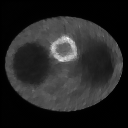

Refer to caption Refer to caption

Figure 9: Images of experiment 4. The images in left and right columns are reconstructed from data sets 1 and 2, while the images in first and second rows are reconstructed by modified versions of TV-superiorized EM algorithms 1 and 2, respectively. From left to right and from top to bottom, the images are labeled as image 1 to image 4 for reference.

Table 4: TV values, l1superscript𝑙1l^{1}-norm, RMSEs and iterations of the images of experiment 4.

image 1 image 2 image 3 image 4

TV(×103absentsuperscript103\times 10^{3}) 25.318 12.931 12.955 7.080

l1superscript𝑙1l^{1}(×103absentsuperscript103\times 10^{3}) 12.404 6.408 7.013 3.399

RMSE 0.1873 0.2772 0.1231 0.1999

iteration 13 8 29 18

Figure 9 displays the reconstructed images by the modified versions of TV-superiorized EM algorithms 1 and 2 in absence of the decreasing condition of TV function. The TV values, l1superscript𝑙1l^{1}-norms, RMSEs and iterations are tabulated in table 4. And figure 10 plots the evolutions of ln(1+βk)1subscript𝛽𝑘\ln(1+\beta_{k}).

As our expectation, the evolution of parameter βksubscript𝛽𝑘\beta_{k} of the modified version of TV-superiorized algorithm 2 is similar to the l1superscript𝑙1l^{1}-superiorized EM algorithm 2, decreasing at much slower rate. However, this modification has very little effect on the TV-superiorized algorithm 1.

It is amazing that the modified algorithms also reduce the TV function (see table 3), even the reconstructed images are better than those reconstructed by the TV-superiorized EM algorithm 2, although we do not validate the decreasing condition of it. The reasons include two aspects. In superiorized algorithms 1 and 2, there are two conditions to control the decreasing of βksubscript𝛽𝑘\beta_{k}, which causes the size of βksubscript𝛽𝑘\beta_{k} is very small at large iterations. Therefore, the strength of regularization is very weak, and the reconstructed image is not good enough. For the modified superiorization algorithms, there is only one condition to control the decreasing of βksubscript𝛽𝑘\beta_{k}, and βksubscript𝛽𝑘\beta_{k} decreases at a lower rate. Therefore, the modified superiorization algorithms can maintain stronger regularization at large iterations, and the reconstructed image is much better. The further study about this algorithm is future work.